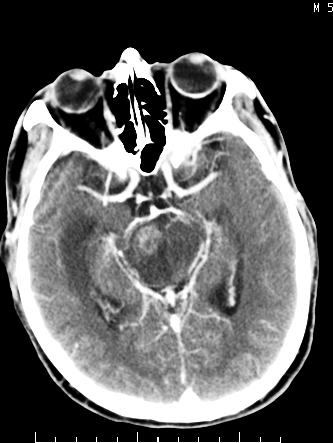

m/50,头昏头痛1月,近3天感觉左半肢体活动不利,自述半年前呈患肺tb,腰穿脑脊液未见特殊改变。现做头颅ct请大家会诊。

首先考虑肿瘤性病变,星形细胞瘤可能性大,不排外转移瘤。建议mri。

结核性脑膜炎,结核瘤,梗塞灶三症并存,提示颅内结核感染可能性大。

请大家结合临床表现看一下 左侧肢体的症状是脑干 还是其他的问题 另外结核感染脑脊液应该有问题 所以应该考虑肿瘤性病变

右侧基底节区缺血性脑梗塞.脑干区考虑结核.

可考虑结核,患者水肿范围大,囊性病灶边缘密度较高,不考虑胶质母细胞瘤